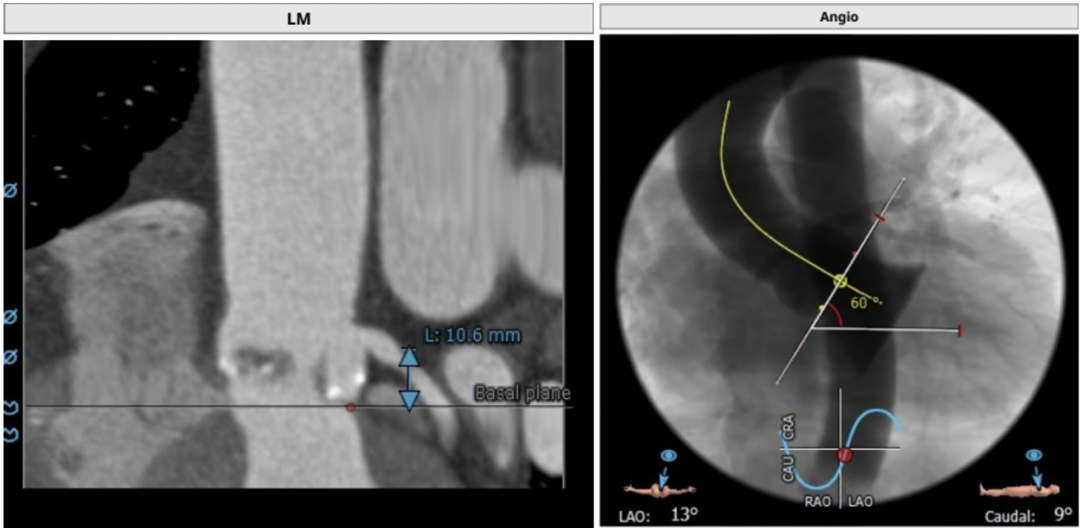

左冠开口高度:10.6 mm,存在冠脉风险;心脏呈横位,角度约为60°

CT评估结果显示,患者为三叶瓣,中度钙化,法式窦结构相对可,右冠高度可,左冠开口高度低,瓣叶上缘达左冠开口下缘,植入主动脉瓣膜后有一定概率压迫冠脉开口,冠脉阻塞风险较高。横位心,心脏角度约60°,左室大小可,升主动脉未见明显扩张。术前CT提示患者术后房室传导阻滞发生概率较高,手术操作复杂风险较大。